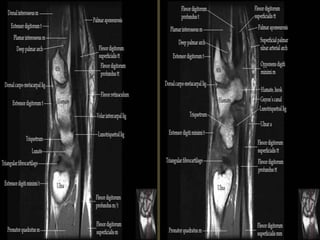

The transverse carpal ligament (short arrows) extends from the hook of the hamate (long

arrow) to the tubercle of the trapezium (arrowhead), forming the floor of the carpal tunnel.

At the radial aspect of the carpal tunnel, the flexor digitorum tendons are arranged in two

rows (separated by dotted line), the profundus tendons deep to the superficialis tendons. The

flexor pollicis longus tendon (star) is positioned at the ulnar aspect of the tunnel, separated

from the flexor carpi radialis tendon (curved arrow) by a ligamentous reflection of the

transverse carpal ligament. The median nerve is indicated (asterisk). - See more at:

http://radsource.us/palmar-bursae-and-flexor-tendon-sheaths/#sthash.mSFX1u0c.dpuf